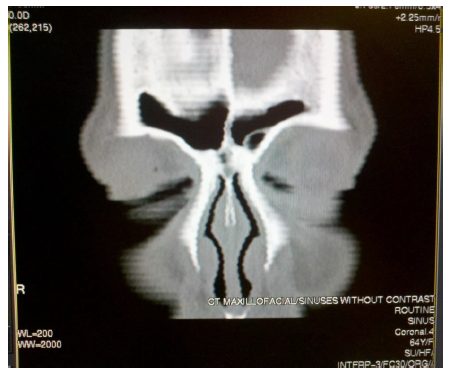

À FAIRE : soyez attentif lors des alignements du tube. Un alignement incorrect du tube peut entraîner des problèmes de qualité d’image. Voici deux exemples d’artefacts d’image possibles résultant d’un mauvais alignement du tube :